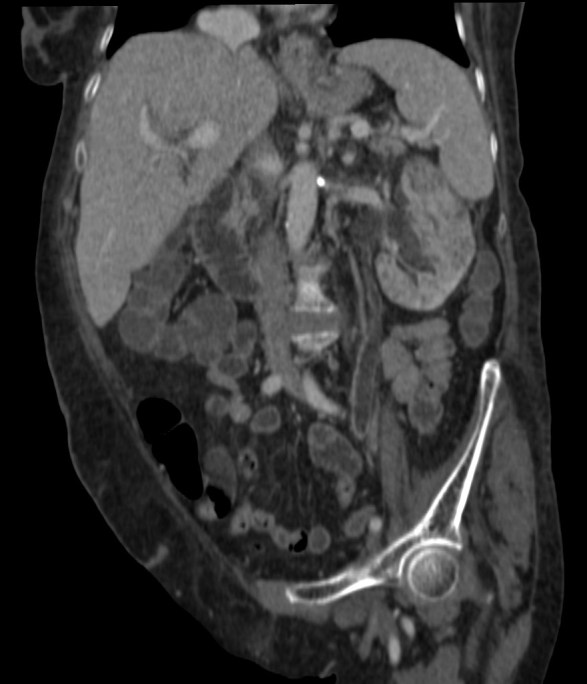

Se procede a realizar TC abdomino-pélvico con contraste en fase nefrográfica y excretora:

Conclusión: se nos presentó un caso de un paciente con una sospecha de infección renal complicada ya que tras cuatro días de tratamiento antibiótico no hubo mejoría. Ante los hallazgos observados en TC, podemos establecer el diagnóstico de pieloureteritis renal izquierda con signos de hidroureteronefrosis leve hasta vejiga.

B- Con el TCMD con contraste en fase excretora podemos estudiar las vías de manera más prescisa y hacer reconstrucciones. Estudio normal.

C- UIV de una hidroureteronefrosis izquierda leve (grado II/IV) hasta vejiga.

- Protocolo: TC abominopélvico sin y con contraste en fase nefrográfica (70 seg) +/- fase tardía ( a los 7 – 10 min) solo si se sospecha obstrucción.

- TC con contraste: Las áreas afectadas del parénquima aparecen como zonas con baja atenuación debido al edema. Las áreas hiperdensas son menos frecuentes y corresponden a focos de hemorragia. Estos hallazgos son mejor valorables a través de la aplicación de contraste, ya que un TC en vacío pueden pasar desaprecibidas.